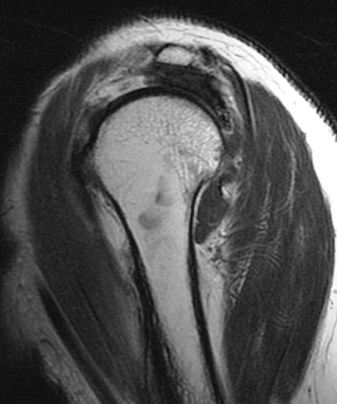

75 y/o s/p dislocation

Dislocation pathology is typically different in older patients than younger patients. The great majority of first time dislocators under the age of 40 suffer a bankart lesion (avulsion of the labral ligamentous complex on the glenoid side). Older folks often suffer a rotator cuff tear including the supraspinatus or subscapularis (or both). This patient had an SST tear but in addition also has a HAGL lesion (humeral avulsion of the glenohumeral (IGHL) ligament). She also has subscapularis partial tearing associated with a near complete dislocation of the biceps (findings that I think were preexisting). Reference article.

HAGL lesion and rotator cuff tears